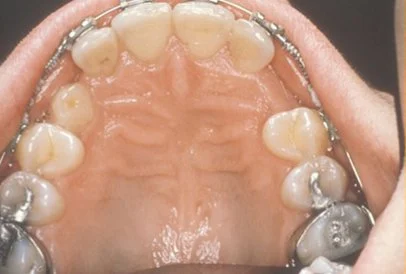

Sixty percent of these impacted eyeteeth are located on the palatal (roof of the mouth) side of the dental arch. The remaining impacted eye teeth are found in the middle of the supporting bone but stuck in an elevated position above the roots of the adjacent teeth or out to the facial side of the dental arch.

In cases where the eyeteeth will not erupt spontaneously, the orthodontist and oral surgeon work together to get these unerupted eyeteeth to erupt. Each case must be evaluated on an individual basis but treatment will usually involve a combined effort between the orthodontist and the oral surgeon. The most common scenario will call for the orthodontist to place braces on the teeth (at least the upper arch). A space will be opened to provide room for the impacted tooth to be moved into its proper position in the dental arch. If the baby eyetooth has not fallen out already, it is usually left in place until the space for the adult eyetooth is ready. Once the space is ready, the orthodontist will refer the patient to the oral surgeon to have the impacted eyetooth exposed and bracketed.

In a simple surgical procedure performed in the surgeon’s office, the gum on top of the impacted tooth will be lifted up to expose the hidden tooth underneath. If there is a baby tooth present, it will be removed at the same time. Once the tooth is exposed, the oral surgeon will bond an orthodontic bracket to the exposed tooth. The bracket will have a miniature gold chain attached to it. The oral surgeon will guide the chain back to the orthodontic arch wire where it will be temporarily attached. Sometimes the surgeon will leave the exposed impacted tooth completely uncovered by suturing the gum up high above the tooth or making a window in the gum covering the tooth (on selected cases located on the roof of the mouth). Most of the time, the gum will be returned to its original location and sutured back with only the chain remaining visible as it exits a small hole in the gum.